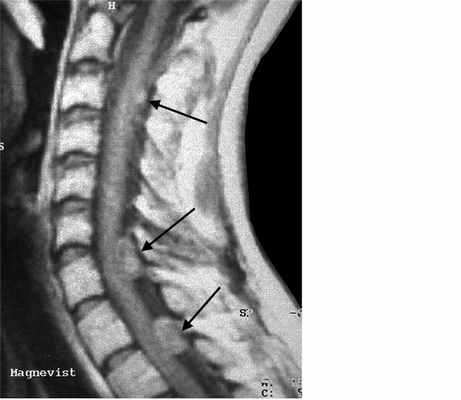

МРТ шейного отдела позвоночника. Нейрофиброматоз тип II. Множественные невриномы (стрелки). Т1-взвешенная МРТ с контрастированием.

Невриномы (шванномы) и нейрофибромы составляют примерно половину опухолей этой локализации и 35% от всех спинальных опухолей. Гистологически невриномы происходят из шванновских клеток оболочек нерва (леммоцитов), прилегающих к заднему корешку. Обычно диагностируются они в возрасте 20 – 50 лет, у мужчин проявляются несколько в более молодом возрасте, чем у женщин. Они почти всегда одиночные, инкапсулированные, располагаются в любом отделе, но чуть чаще в поясничном или верхнем шейном. Множественные невриномы встречаются исключительно редко при нейрофиброматозе типа II. Нейрофибромы состоят из шванновских клеток и фибробластов, некоторые окружают задний корешок. Они почти всегда множественные и связаны с нейрофиброматозом типа I (болезнь Реклингхаузена). От 2 до 12% нейрофибром перерождаются злокачественно, превращаясь в нейрофибросаркомы. Несмотря на различие в гистологии характер роста опухолей одинаковый. Около 15% из них распространяются в экстрадуральное пространство через одно или несколько межпозвоночных отверстий, приобретая вид “песочных часов”. Такой тип роста особенно типичен для шейной локализации. На рентгенограммах рост по типу «песочных часов» может быть выявлен по расширению межпозвоночного ответстия и эрозии корня дуги. Клинические проявления неврином и нейрофибром состоят в радикулопатическом и миелопатическом синдромах.

На МРТ Т1-взвешенного типа и невриномы, и нейрофибромы изо- или слегка гипоинтенсивны по отношению к спинному мозгу. Однако, встречаются случаи и повышенного сигнала за счет сокращения Т1 мукополисахаридами, связанными с водой. Протонная плотность при МРТ повышена, а на Т2-взвешенных МРТ они чаще неоднородные, могут быть очень яркие участки, где имеется высокое содержание воды, и сравнительно низкого сигнала, особенно в центре. Обе опухоли хорошо контрастируются при МРТ. По форме невриномы округлые, границы ровные, четкие. Нейрофибромы вытянуты вдоль корешка, что лучше видно на корональных МРТ. Размеры могут быть самыми различными.